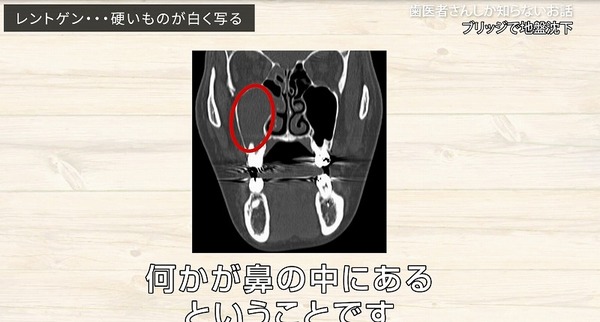

これは

鼻の部屋を分けている

硬い骨です。

そして反対側です。

左側のはっきりくっきりした線に比べると

右側は

途中までははっきりした線がありますが

しかし赤丸の一番大きい歯のところは

はっきりと線が見えません。

人間の体は

だいたい左右対象的ですから

本来の鼻のラインはどこか?

ちょっと右と左でうつり方が違いますね。

本来ならば硬い骨よりも

口側に

歯の根っこや骨が入っていないといけません。

もちろんCTなどで立体的に見れば

そうなのかもしれませんが

平面のレントゲン写真では重なってしまっていて

そのようにうつってくることもあります。

何かが鼻の中にある

というところですね。

副鼻腔

上顎洞の中の場所になりますので

副鼻腔炎

という病名がつきます。

もっと見てみると

少し歯の根っこが

鼻の部屋に入り込もうとしています。

こちらはどうでしょうか?

完全に鼻の中に

歯の根っこがめり込んでしまっています。

硬い骨があって

歯の根っこがどんどん

突き上げられていって

突き抜けている

ということが

わかります。